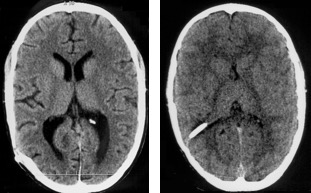

le scanner ou l’IRM montre une dilatation ventriculaire, mais il est important de connaitre la taille ventriculaire de base en disposant du scanner de référence

- si l’imagerie présente suggère une obstruction (ci-contre)